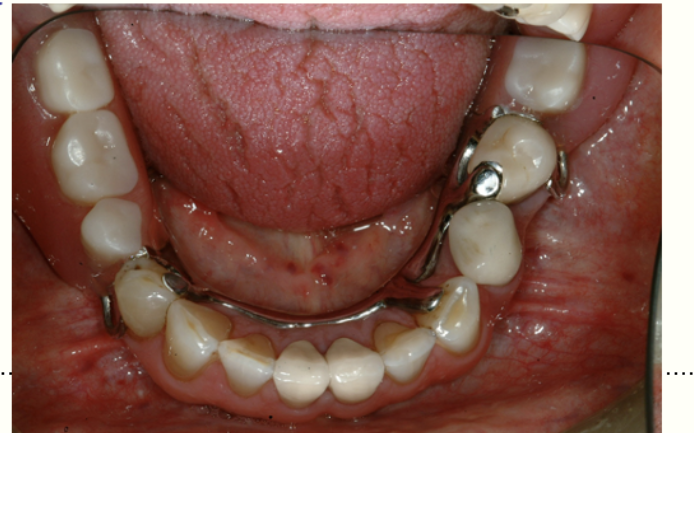

14

Q

what type of denture is this

A

Class II